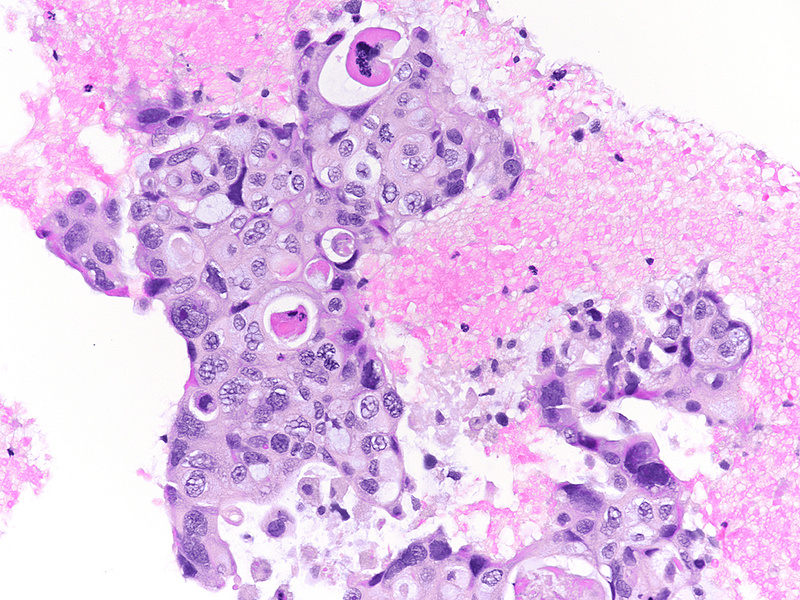

The well-sampled biopsy showed fragments of a necrotising carcinoma, arranged in isolated cells, small aggregates of cells and poorly formed glandular structures (Panels A-B). The tumour cells demonstrated abundant eosinophilic cytoplasm and severely pleomorphic, hyperchromatic nuclei with distinct nucleoli. Brisk mitotic activity was noted (Panel C). Within some clusters, the neoplastic cells had a more polygonal appearance, with intercellular desmosomes, more basophilic cytoplasm and evidence of dyskeratosis (Panels D-E).